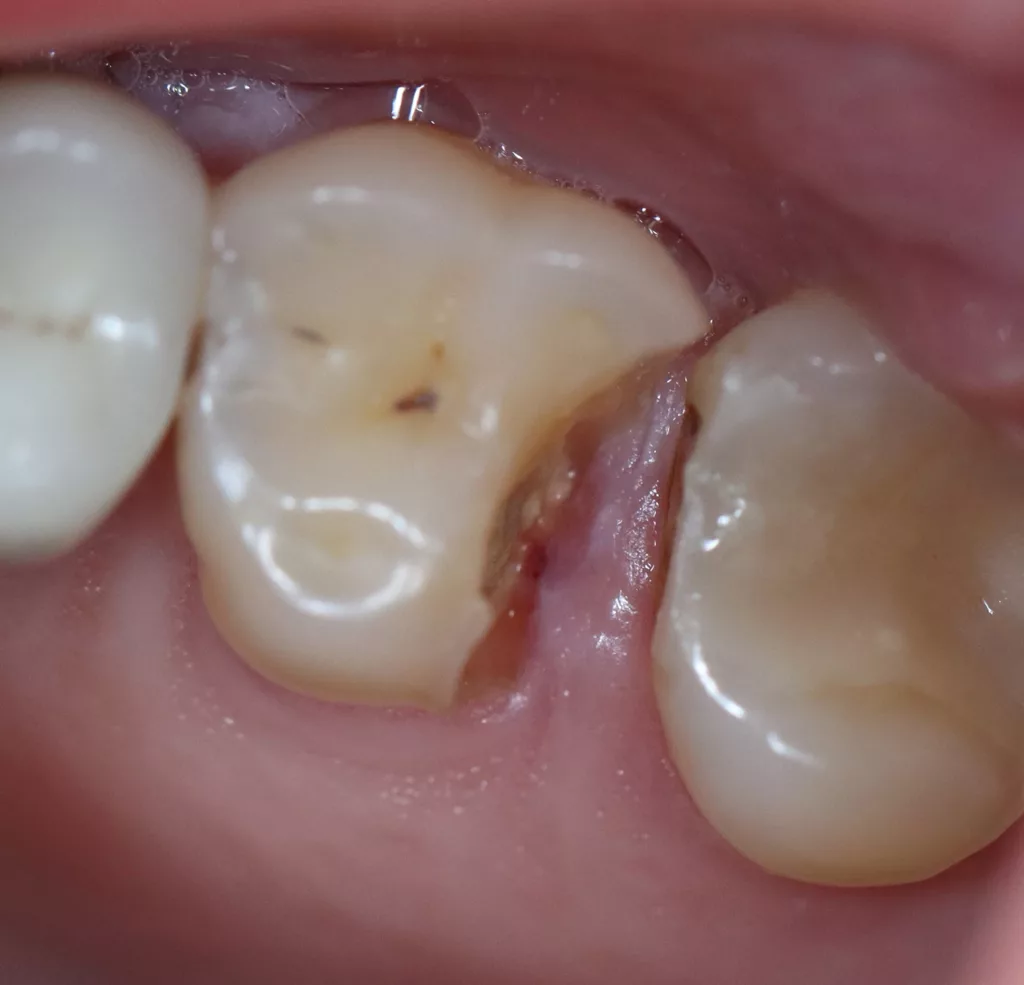

Wird eine profunde kariöse Läsion behandelt, empfiehlt sich folgendes Vorgehen [5]: Zunächst sollte in einem ersten Schritt ein Kofferdam appliziert werden, um eine möglichst keimfreie Arbeitsweise zu gewährleisten. Nach Präparation einer Zugangskavität, wenn dies notwendig ist, erfolgt die Kariesexkavation mittels Rosenbohrern oder Handexkavatoren. Wird in pulpanahen Arealen eine Eröffnung der Pulpa erwartet, sollte das Instrument gewechselt und ein sauberer Rosenbohrer genutzt werden. Tritt nach vollständiger Kariesexkavation keine Eröffnung der Pulpa ein, ist aber von einer dünnen Restdentindicke von etwa 300 µm auszugehen, oftmals erkenntlich durch eine zartrosa hindurchschimmernde Pulpa, sollte nach Kavitätentoilette mittels Natriumhypochlorit (NaOCl) 3% eine indirekte Überkappung mit einem hydraulischen Kalziumsilikatzement erfolgen [5]. NaOCl dient dazu, Bakterien und Toxine zu neutralisieren und das Dentin zu desinfizieren. Die Unterfüllung aus Kalziumsilikatzement soll auch desinfizierend wirken, das Pulpagewebe zur Heilung anregen und vor möglicherweise durch das Dentin penetrierenden Monomeren aus dem Dentinadhäsivsystem schützen [5], da diese die regelrechte Funktion der Odontoblasten beeinträchtigen können [9,40]. Im Anschluss muss eine direkte, dentinadhäsive Restauration zur Versorgung der Kavität platziert werden [5]. Die Abbildungen 1 bis 14 illustrieren das Vorgehen bei der Behandlung einer profunden kariösen Läsion mit indirekter Überkappung der Pulpa.